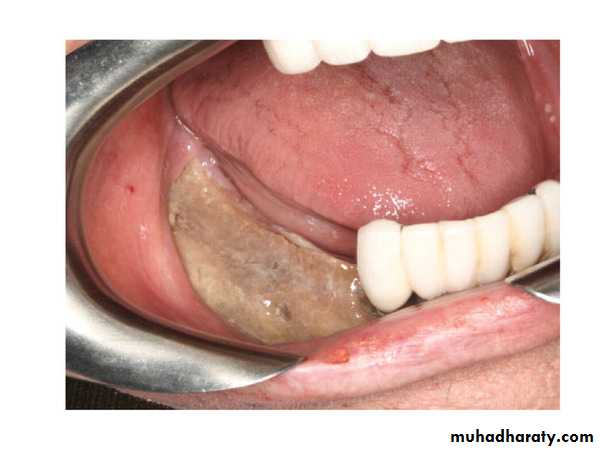

Osteoradionecrosis (ORN); it is a late complication that arise after radiotherapy, it is a state of hypocellularity, hypovascularity and hypoxia of the irradiated jaw bones, characterized by exposed bone that fails to heal. Factors that may increase the incidence of ORN:

1. Dentate patient.

2. Mandible, especially posterior region.

3. Dose of radiation, the risk of ORN is greater when the dose exceeds 6500 cGy.

4. Patients who continue smoking.

5. Trauma (like extraction).

6. Infection.

If ORN occurs, its management is:

1. Daily irrigation of the exposed bone by normal saline, antiseptic or antibiotic solutions.

2. Conservative local surgical debridement (trimming of the sharp edges of the sequestra) to avoid further trauma.

3. Broad spectrum antibiotics.

4. Severe cases may require hyperbaric Oxygen.